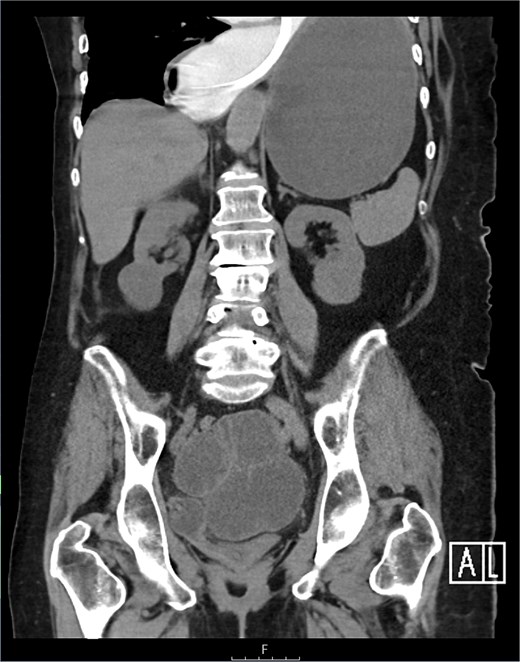

The CT also showed a large ventral hernia in the anterior abdominal wall on the left side, with several entrances and exits for intestinal loops within the hernia. The proximal loops appeared dilated up to 5 cm, with fat stranding and slight fluid between the loops, as well as mild prominence of the mesenteric blood vessels. Distal loops were collapsed, raising suspicion of high-grade obstruction with ischemic bowel involvement (Fig. 5).

CT axial view—obstructed ventral hernia with proximal small bowel loop dilatation.